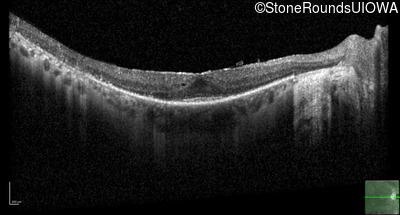

Optical Coherence Tomography - Right - 20/25 -2 sc

Exemplar / OCT Stack

OCT Stack